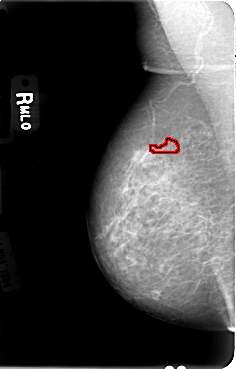

FILE: B_3030_1.RIGHT_MLO.OVERLAY

TOTAL_ABNORMALITIES 1

ABNORMALITY 1

LESION_TYPE CALCIFICATION TYPE PLEOMORPHIC DISTRIBUTION CLUSTERED-LINEAR

ASSESSMENT 4

SUBTLETY 3

PATHOLOGY BENIGN

TOTAL_OUTLINES 1

BOUNDARY